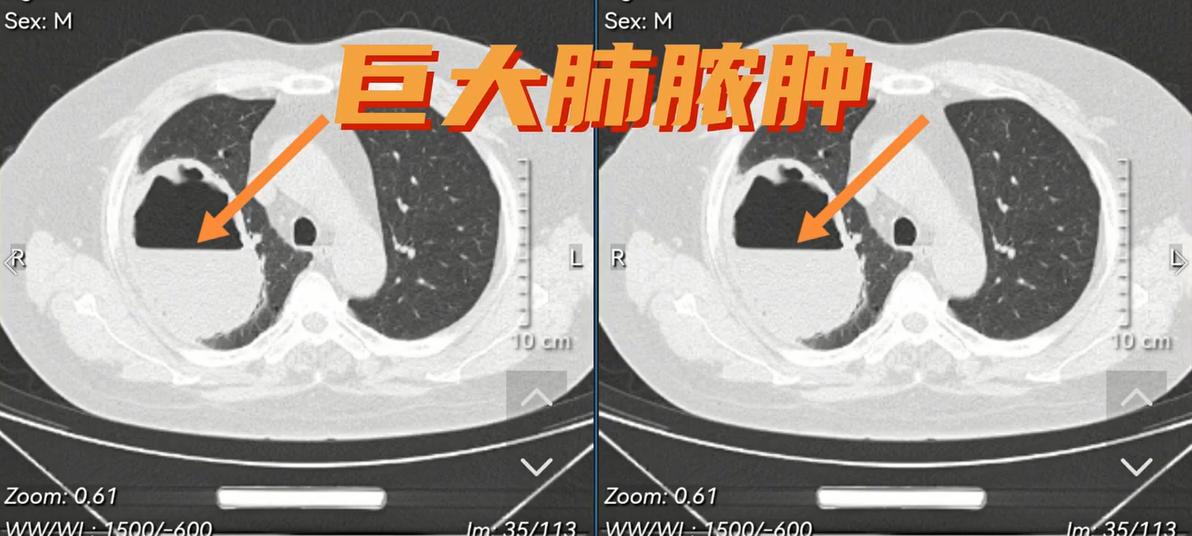

12月5日前往医院看病,经肺部CT检查后,发现肺里有一个巨大的洞,这个洞医学上称为“肺脓肿”,杨女士住院抗菌治疗结合脓液引流,治疗7天后空洞明显缩小。

杨女士治疗前CT空洞

肺脓肿在CT中的典型表现: 空洞大小不一、空洞可单发也可多发、空洞边缘光滑,合并感染时壁增厚而边缘模糊、可见中等或大量脓液。